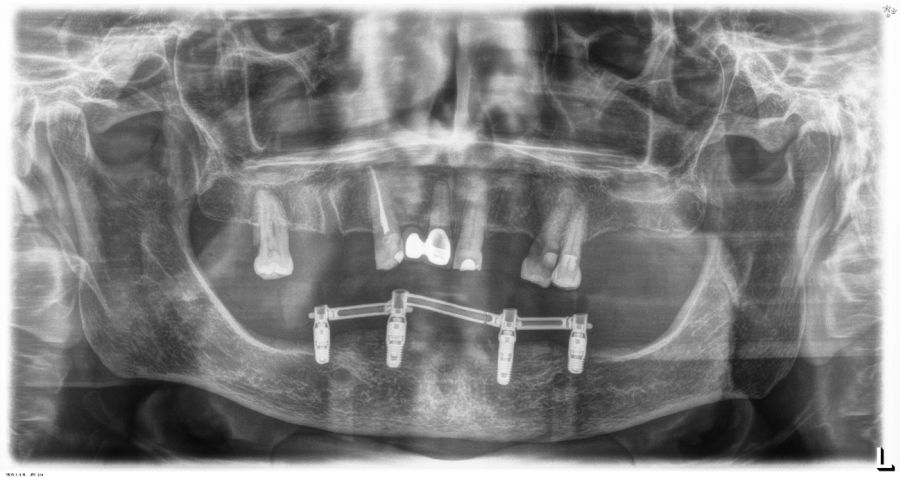

El análisis global de los 99 implantes reveló una pérdida ósea marginal media de 0,77 ± 0,26 mm en la superficie mesial y 0,79 ± 0,29 mm en la distal, valores que se mantuvieron dentro de los rangos considerados clínicamente aceptables para rehabilitaciones mandibulares. Cuando los implantes se categorizaron según su longitud, se observaron diferencias claras entre ambos grupos. Los implantes cortos (<10 mm) mostraron una pérdida ósea mesial media de 0,61 ± 0,23 mm y distal de 0,56 ± 0,22 mm, mientras que los implantes largos (≥10 mm) presentaron pérdidas significativamente mayores (mesial: 0,92 ± 0,19 mm; distal: 0,99 ± 0,17 mm). Dado que las pruebas de normalidad (Shapiro–Wilk) mostraron una distribución no normal en todos los grupos (p < 0,001), se aplicó la prueba no paramétrica de Mann–Whitney U. Los resultados confirmaron diferencias estadísticamente significativas tanto en la pérdida ósea mesial (U = 2068,5; p < 0,001) como en la distal (U = 2247,0; p < 0,005), indicando que los implantes cortos presentaron un comportamiento óseo más favorable que los implantes largos a lo largo del tiempo. Durante el tiempo de seguimiento que fue de media de 12,2 años (+/- 4,4; rango 6-23 años) no se objetivaron fracasos en ninguno de los implantes por lo que la supervivencia acumulada fue del 100%. El análisis del periodo de seguimiento mostró diferencias claras entre ambos grupos. Los implantes largos (≥10 mm) presentaron un tiempo medio de función de 14,1 ± 4,2 años (rango: 9–23 años), mientras que los implantes cortos (<10 mm) registraron un seguimiento significativamente menor, con una media de 9,8 ± 2,7 años (rango: 6–15 años). En las Figuras 3- 10 se muestran dos casos incluidos en el estudio, uno de cada situación descrita.

Un aspecto clave para interpretar estos resultados es el tiempo de seguimiento, ya que en nuestra cohorte los implantes largos presentaron significativamente más años en función intraoral. El análisis del periodo de seguimiento mostró diferencias claras entre ambos grupos. Los implantes largos (≥10 mm) presentaron un tiempo medio de función de 14,1 ± 4,2 años (rango: 9–23 años), mientras que los implantes cortos (<10 mm) registraron un seguimiento significativamente menor, con una media de 9,8 ± 2,7 años (rango: 6–15 años). La comparación mediante la prueba de Mann–Whitney U reveló diferencias estadísticamente significativas entre ambos grupos (p < 0,001). Este mayor tiempo en función de los implantes largos constituye un factor relevante a considerar en la interpretación de las diferencias observadas en la pérdida ósea marginal. La literatura demuestra que la pérdida ósea crestal es más pronunciada durante los primeros 12 meses y tiende a estabilizarse posteriormente, aunque existe un remodelado lento y continuo asociado al tiempo 36,48–50. Por tanto, es plausible que parte de la mayor pérdida ósea observada en los implantes largos esté relacionada con el mayor periodo de observación, aunque con los datos y el análisis realizado en el presente estudio, no podemos establecer esta correlación. Este factor debe considerarse al comparar ambos grupos y será analizado en estudios futuros con modelos de regresión ajustados por tiempo.

Por otro lado, la ausencia de fracasos implantares en ambos grupos es especialmente destacable, ya que la rehabilitación completa sobre cuatro implantes ha sido históricamente objeto de preocupación biomecánica, tanto por la carga concentrada como por la presencia potencial de cantilevers en las prótesis12,15. En técnicas como el All-on-4 descrito por Malo, donde los implantes distales se angulan 30–45°, se han reportado supervivencias elevadas, pero también mayores tasas de complicaciones mecánicas y protésicas, especialmente relacionadas con la sobrecarga distal y la fatiga del tornillo o de la estructura13,47. En contraste, la estrategia utilizada en este estudio, basada en cuatro implantes paralelos, cortos o largos según la disponibilidad ósea, reduce la complejidad biomecánica y distribuye las cargas de forma más homogénea, minimizando los momentos de flexión sobre los implantes distales18. La capacidad de los implantes cortos para sostener rehabilitaciones completas ha sido respaldada por múltiples estudios. Diferentes trabajos de la literatura internacional han demostrado que los implantes cortos (≤8 mm) alcanzan supervivencias comparables a los convencionales y presentan tasas similares de complicaciones mecánicas, siempre que se respeten principios biomecánicos como la ferulización rígida, la correcta pasividad protésica y la ausencia de cantilevers excesivos21,22,35–41,51–56. Los resultados de este estudio refuerzan esta evidencia, mostrando que los implantes cortos no solo no incrementan la pérdida ósea, sino que pueden presentar un comportamiento marginal más estable en el largo plazo.

En relación con el voladizo, en nuestra cohorte únicamente las prótesis soportadas por implantes largos presentaban un mayor cantilever distal, mientras que las rehabilitaciones basadas en implantes cortos no lo requerían o tenían uno de longitud mínima. La literatura indica que la presencia de cantilever puede aumentar de forma significativa las tensiones sobre los implantes distales y favorecer el remodelado óseo marginal12,15,57–60. Este hecho podría contribuir a explicar las mayores pérdidas óseas del grupo de implantes largos, al margen del dato del tiempo de seguimiento anteriormente discutido y subraya la relevancia clínica de planificar rehabilitaciones sin voladizo siempre que la anatomía y los implantes cortos lo permitan. Finalmente, la estabilidad de las rehabilitaciones en ambos grupos confirma que el protocolo estandarizado aplicado en esta serie constituido por fresado biológico, carga progresiva y estructura híbrida atornillada sobre transepitelial, con implantes siempre paralelos, sin inclinaciones distales, proporciona un entorno favorable para la osteointegración y el mantenimiento periimplantario a largo plazo. Este enfoque coincide con las tendencias actuales hacia tratamientos mínimamente invasivos, pero biomecánicamente sólidos, reduciendo la necesidad de angulaciones extremas o regeneraciones complejas sin comprometer los resultados clínicos30,32,61,62.